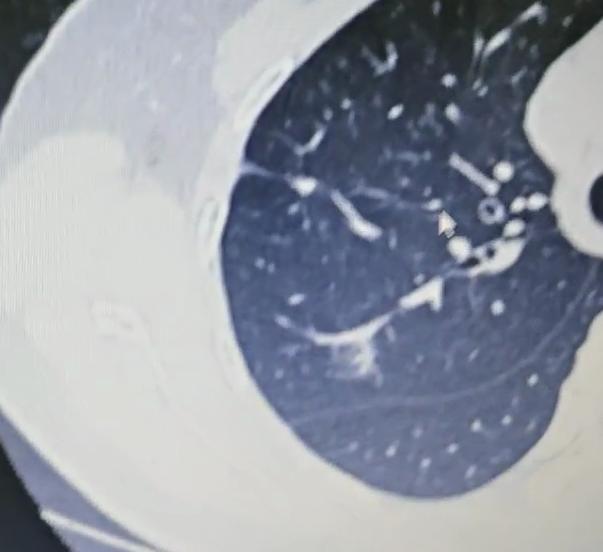

2008年,作家马原患癌,他只做了1次肺部穿刺,就决定放弃任何治疗。跟妻子到云南生活14年后,老天却带走他的小儿子。 2022年, 南糯山的雨季格外漫长。一个阴沉的傍晚, 马原13岁的儿子马格在卫生间突然倒地, 等救护车辗转一个小时赶到山上时, 这场意外已经无法挽回。此后很长一段时间里, 山里的风声在他耳里, 都像是儿子的呼喊。 这个曾在八九十年代叱咤文坛的先锋派作家, 早已把自己藏进大山。很少有人知道, 在丧子之前, 他已经和病魔对峙了十几年。 2008年, 他被查出肺部肿瘤, 穿刺一次就痛得几乎崩溃。医生建议继续检查并尽快治疗, 他却在权衡良恶性的不同结局后, 选择不再做任何进一步手术, 不愿在冷冰冰的时间表里数着日子。 做出这个近乎任性的决定时, 马原已结束上一段婚姻多年。那之前, 他是能连举一百九十多斤杠铃的东北汉子, 也是在辽宁大学中文系沉潜十年、以“叙事圈套”立足文坛的大腕, 和作家皮皮的婚姻一度被视作才子佳人。 病痛与离异让他遍体鳞伤, 直到遇见比自己小二十多岁的退役运动员李小花, 生活才再度亮起来。 小花身上带着阳光, 说话大大咧咧, 完全不同于他笔下的冷峻叙事。她爽快接受表白, 很快跟他领证, 又在他确诊后坚持办了一场婚礼。 婚礼散去的晚上, 小花含着泪说想要一个孩子, 马原答应了。2009年, 马格出生, 这个迟到的儿子让他在阴影中看到了光。 为了陪妻儿久一点, 他跟学校谈妥停课, 带小花先到海南, 戒烟戒酒, 每天沿海骑行, 身上的带状疱疹慢慢结痂脱落。身体好转, 文思复苏, 他写出了《牛鬼蛇神》。2012年, 一家人又来到西双版纳南糯山, 对这里一见钟情。 南糯山姑娘寨有一所废弃小学, 马原把它买下, 花了几年时间盖起九栋房子, 取名“九路马”, 自嘲式地叫它“马堡”。院里种茶种菜, 房间以喜欢的作家命名, 山风一吹, 书页翻动。纪录片《文学的日常》定格下他们一家三口在山林间的日常, 那时没人想到, 这也是某种告别。 在这片茶山里长大的马格, 比同龄人更安静也更敏锐。正规念书不过三年, 成绩却不差。 十三岁的他已经一米八五, 在树林间奔跑, 写下数万字散文与小说, 还写过《我的爸爸叫马原》, 用稚嫩却清澈的笔触打量这个隐居的父亲。镜头里, 他拿着相机拍短视频, 记录雾气缭绕的山谷和鸡犬相闻的院子。 命运的阴影其实早早笼罩过来。马格被发现心脏有问题, 又有人怀疑是马方综合症。李小花想带他去大医院彻查, 马原却本能地抗拒, 总觉得自己当年是在远离医院、回到自然后一点点好起来的, 儿子或许也能靠这样的生活慢慢扛过去。 夫妻俩一边在山中小心照看, 一边又带着孩子四处问医, 在希望与担忧之间反复拉扯。 真正的那一天来得猝不及防。卫生间里闷响一声, 孩子倒下, 山路狭窄, 救护车迟迟不能抵达。等一切归于寂静, 南糯山的云海照旧翻滚, 马堡的窗子照旧透出灯光, 但这个家再也不完整了。 几年后, 马原在悼文里只写思念, 不提原因。他知道, 自己当初相信顺其自然、相信山林能疗伤的选择里, 也有躲避和侥幸。世事无常, 本以为癌症会先带走自己, 却偏偏是儿子先行一步。 此后, 他更加沉入写作, 像是在纸上与马格对话。小花则开始帮助山里那些上学困难的孩子, 把有限的积蓄分到别人家的书包里。对她来说, 这是另一种方式的延续。 从文坛锋芒毕露的先锋作家, 到带病隐居山林的“筑堡人”, 再到白发苍苍的失独父亲, 马原的人生一再被命运改写。 南糯山的风一天天吹过, 他常说, 人的一生就像四季, 有春的萌动, 有夏的丰盛, 也有秋的凋零和冬的寂静。重要的不是逃避哪一季, 而是在每一个当下, 尽量不辜负眼前的人。 马格的离开, 像是一笔被提前收回的幸福贷款。留下来的那个人, 只能在余生里反复偿还, 用更认真地活下去, 来记住那个曾经在山林间奔跑的孩子。